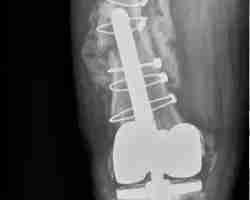

Dr. Morton is a hip and knee specialist who provides clinical and surgical services. His focuses are on joint replacements, complex reconstruction, robotic-assisted surgery, sports surgeries, and trauma care.